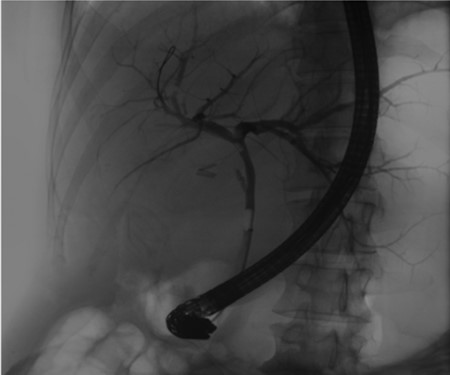

Independent biliary duct (blue arrow) draining to the cyst and not to the liver parenchyma.

A 35-year-old female with a medical history significant for acute biliary pancreatitis status post laparoscopic cholecystectomy, presented to the surgery clinic as a new consult for a large cystic liver mass with increasing abdominal pain for 2 weeks. Patient reported suffering from severe pain in right chest, shoulder and diffuse abdominally that worsened with standing. Patient complained of inability to inspire due to pain and a 10-pound weight gain over 2 months. She confirmed decreased appetite especially with solids, nausea and emesis, alternating constipation and diarrhea, bruising, and pruritus at night. Computed tomography (CT) scan demonstrated a peripherally septated 10 x 7 cm cystic mass in the liver with intrahepatic biliary dilation (Fig. 1). The patient was referred for endoscopic retrograde cholangiopancreatography (ERCP) to establish preoperative biliary anatomy and was found to have moderate compression of the common hepatic duct managed with a right hepatic biliary endoprosthesis (Fig. 2); no obvious communication of the biliary tree with the cystic lesion was seen. Patient symptoms persisted despite optimizing with a protein-rich liquid diet; thus, the decision was made to proceed with the surgical plan for an open partial central hepatectomy. The patient was taken to the operative theater. After induction of general anesthetic, an upper midline incision was made. Inspection of the abdomen and liver showed no metastatic lesions grossly or with ultrasonographic imaging. The cyst was visible upon entry into the abdomen with no solid component to the mass in proximity to the cystic neoplasm. The second portion of the duodenum was adherent to the cyst with inflammatory adhesions and was quite boggy. A partial central hepatectomy was performed; a 3 mm biliary duct was found communicating to the cyst only with no drainage to the minimal liver parenchyma that was removed (Fig. 3). The cyst was resected en-bloc and was sent for permanent section (Fig. 4), which diagnosed the tumor as a low-grade mucinous cystic neoplasm measuring 8.5 × 7.2 × 6.4 cm. Microscopy revealed a smooth-walled, multiloculated cyst filled with a yellow-golden, semi-transparent and mucinous fluid (Fig. 5a–c). The cyst was lined by a mucinous epithelium with ovarian-type stroma. No high-grade dysplasia or malignancy was identified. The postoperative course was uneventful, and the patient was discharged on postoperative day 6. At the 4-week postoperative visit, the patient was healing well with some incisional soreness; patient was seen for removal of her biliary endoprosthesis, and ERCP found left sided intrahepatic duct biliary dilatation including a small biliary fistula from the left system (Fig. 6) with the appearance of torque on the extrahepatic biliary tree. A biliary endoprosthesis was left in place, and the patient returned for repeat ERCP 4 weeks later with resolution of all findings (Fig. 7). At present, patient remains alive with no signs of recurrence.